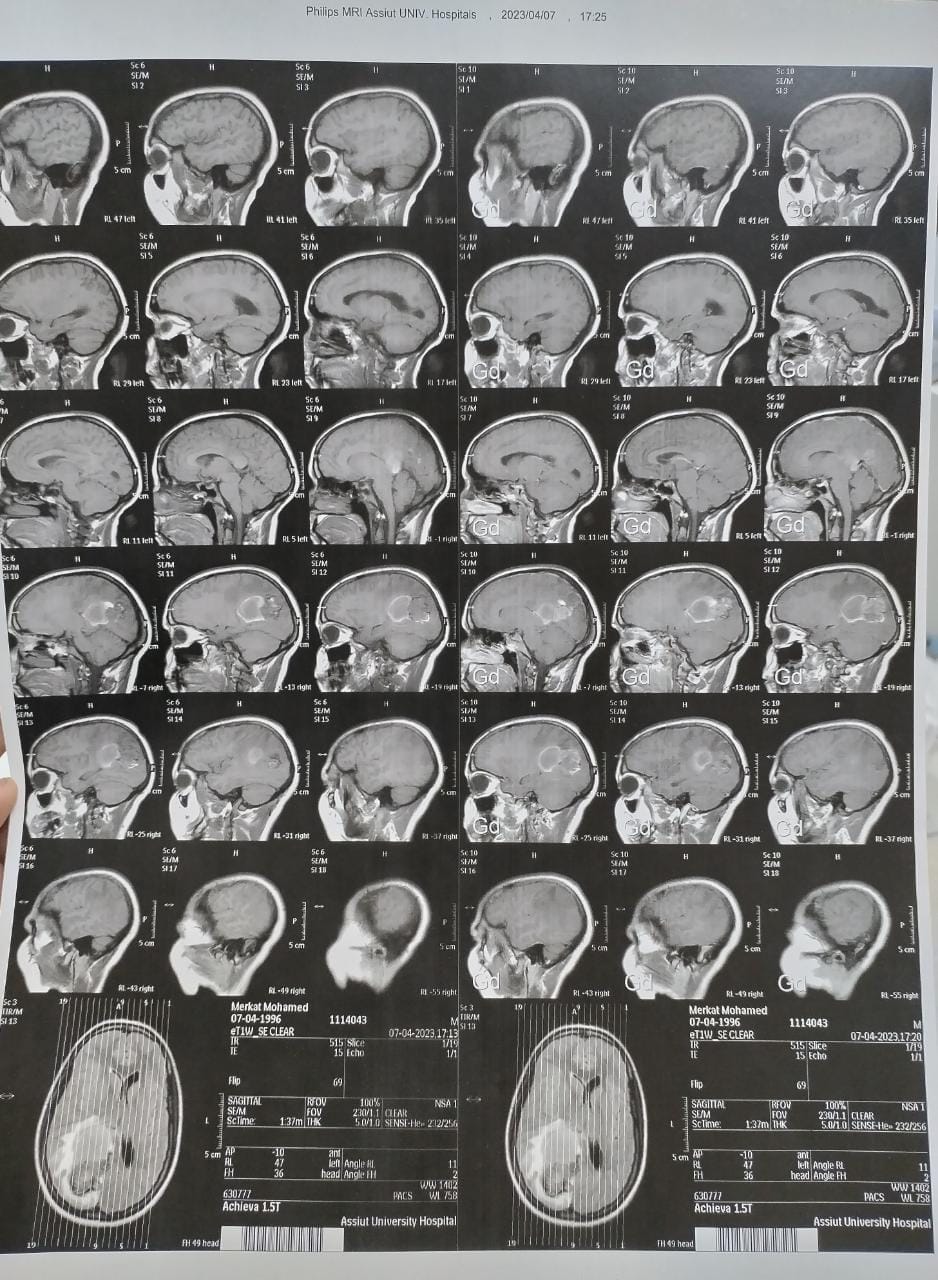

أجرى الفريق الطبي بنجاح جراحة لمريضة عمرها ٢٨ عاما تعاني من صداع مستمر، وبمناظرة الأشعات تبين وجود وحمة دموية كبيرة نافذة ضاغطة على مركز الحركة، وعلى الفور تشكل قام الفريق الطبي بقيادة الدكتور محمد عبد الباسط خلاف رئيس قسم جراحة المخ والأعصاب ومدير المستشفى، يعاونه الدكتور محمد سيد عبد العال مدرس التخدير والعناية المركزة، والطبيب مصطفى كاشف مدرس مساعد جراحة المخ والأعصاب، وتم إجراء الجراحة و استئصال كامل للوحمة الدموية، بواسطة الميكروسكوب الجراحي وجهاز الأشعة التليفزيونية على المخ مع الحفاظ على جميع المراكز الحساسة بالمخ، وقد توجه الفريق الطبي بالشكر إلى هيئة التمريض المعاونة.